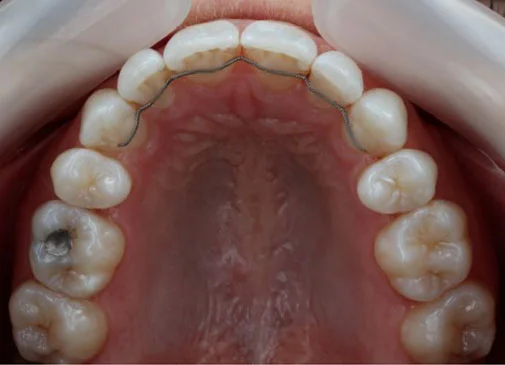

Our amazing Invisalign results

If you’re wondering whether Invisalign can really make a difference, simply take a look at these images below.

Case 5:

![]()